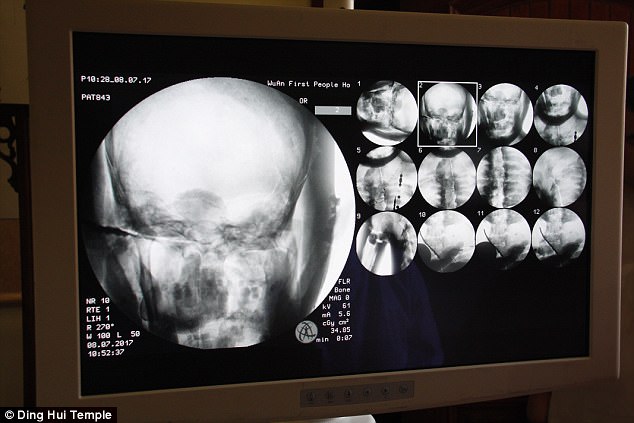

Sự kiện gây chấn động diễn ra vào ngày 8 tháng 7 năm 2017, khi các nhà khoa học tiến hành chụp CT để kiểm tra bên trong "bức tượng" này trước sự chứng kiến của giới truyền thông và đông đảo người dân. Kết quả hình ảnh quét được đã khiến tất cả những người có mặt phải bàng hoàng. Các bác sĩ xác nhận rằng bên dưới lớp mạ vàng, nhà sư Ci Xian vẫn giữ được bộ xương nguyên vẹn cùng một bộ não hoàn chỉnh.

Bác sĩ Wu Yongqing, người trực tiếp tham gia buổi kiểm tra cho biết xương của ngài khỏe mạnh và rõ ràng như một người bình thường. Từ xương hàm trên, răng, xương sườn, xương sống cho đến tất cả các khớp đều vẫn còn nguyên vẹn một cách khó tin. Sự tồn tại hoàn hảo của thi hài sau hơn 1.000 năm đã chứng minh kỹ thuật ướp xác đỉnh cao thời bấy giờ, tạo nên một hiện tượng chấn động khiến cả thế giới phải chú ý.

Những hình ảnh có được sau khi chụp CT